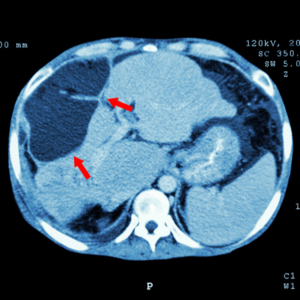

*上图和封面图为获得摄图新视界©️版权图片,图中上腹部CT扫描:显示肝脏异常肿块